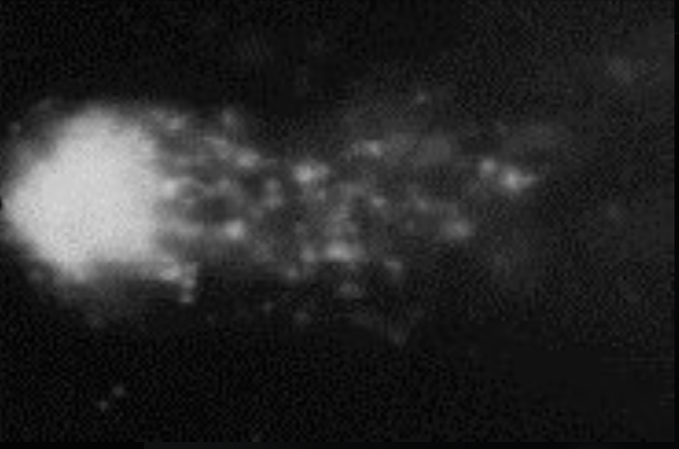

Comet assay: X-ray Calibration (25.6 rads)

X-ray Exposed Cell (Calibration)

Rat brain cells exposed to 25.6 rads of ionizing X-ray radiation. Notice the pronounced comet tail: a bright “head” with most of the DNA, and a long trailing “tail” of smaller fragments migrating under an electric field.

• Ionizing radiation (X-rays) produces both single-strand and double-strand breaks.

• This image is used as a calibration standard—comet tail length roughly correlates with X-ray dose.

• Shows classic severe DNA fragmentation from high-energy photons.